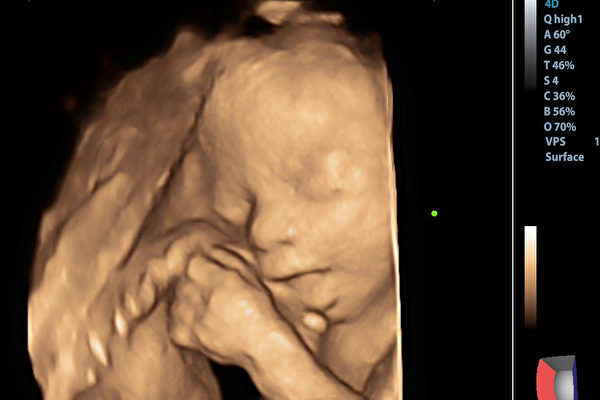

In early October 2024, Ms. Hou received ovulation stimulation drugs. By the end of October 2024, she successfully became pregnant. On November 12, 2024, a hospital examination revealed that there were nine gestational sacs in Ms. Hou’s uterus.

According to a report by the Nanchang Evening News on January 7, Mr. Hu revealed that even after multiple reduction procedures, the remaining two embryos in Ms. Hu’s abdomen could not be saved.